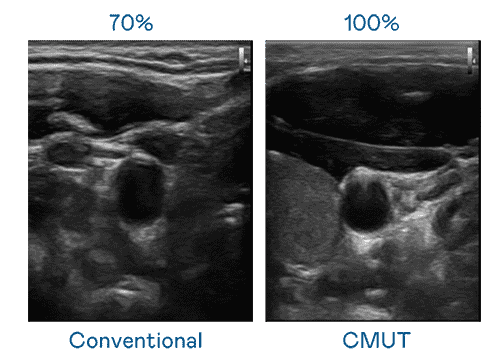

CMUT 技术是一种用电容式微机电元件来产生超音波讯号的技术。。。。与传统 PZT 压电式技术相比,,,,CMUT 频宽增加 30%,,,,更宽频的超音波讯号让影像解析度大幅提升,,,是实现高影像品质医疗超音波扫描、、、、促进精准医疗发展的关键技术。。。

超音波影像的解析度高低,,,,首先取决于探头能发出的讯号频宽。。开云电子 CMUT 可提供高清晰的超音波讯号,,,提供高频宽、、、、高灵敏度、、影像纹理细节更高的超音波影像,,协助医护人员缩短影像判读时间及利用精准的医疗影像进行诊断。。。